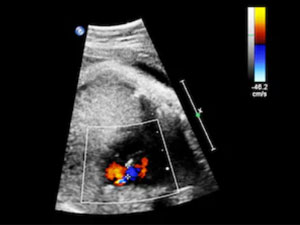

caga dusmesiTürkmenistanyň Saglygy Goraýyş we Derman Senagaty Ministrliginiň işläp düzen kliniki beýanlaryna görä "çaga düşmesi – bu ene bedeninden embrionyň ýa-da düwünçegiň göwreliligiň 22 hepdesine çenli özbaşdak düşmegidir". Möhletine görä irki (12 hepdä çenli) we giçki (13 hepdelikden 22 hepdelige çenli) düşükler tapawutlandyrylýar. 22-nji hepdede ýa-da ondan soň enesiniň içinde ölýän çaga "çaganyň öli dogulmasy ýa-da antenatal ölümi" diýilýär.

Hemme anyklanan göwrelilikleriň arasyndan göwreliligiň özbaşdak düşmeginiň ýygylygy 15-20% deň bolup durýandyr. Hemme düşükleriň arasyndan, irki möhletlerde (6-8 hepdede) bolup geçýän düşükleriň ýygylygy 40-80% düzýändir. Göwreliligiň möhletiniň ulalmagy bilen özbaşdak düşmeleriň ýygylygy hem peselýändir.